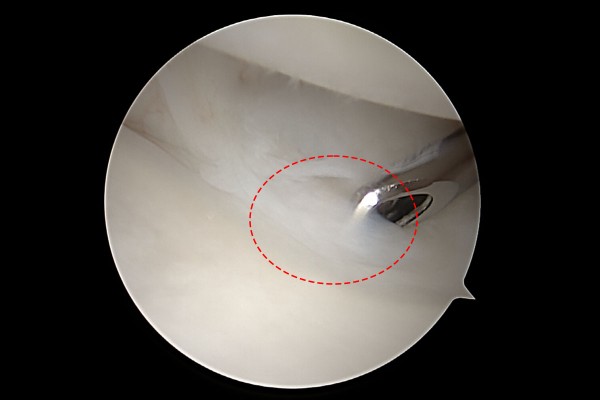

병력청취 후 신체진찰을 위해 새끼손가락측 손목을 눌렀을 때 통증(압통)이 발생하였고, 손목을 가측으로 누르면서 돌렸을 때 역시 통증이 발생한 것을 확인하였습니다. 정확한 상태를 파악하기 위해 환자분께서 지참해오신 MRI 사진을 봤을 때, 삼각섬유연골 복합체(TFCC) 부근에 하얗게 신호변화를 확인하여, 손목 인대파열이 아닌 우측 손목 가측 삼각섬유연골 복합체 손상(TFCC injury wrist Rt.)을 진단하였습니다.

e2dae621a1572a5ea8be78c4dc6d0de9_1768291778_8095.jpg

내시경 사진을 보시면 손목 관절 벽쪽에 빨간 활액막염이 확인됩니다.